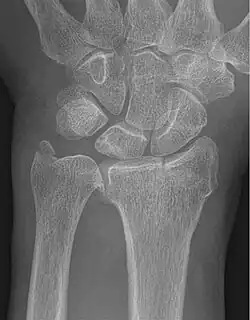

| Fracture of the radial styloid process with the fracture line extending into the intraarticular surface | |

| X-ray of a displaced intra-articular distal radius fracture in an external fixator. The articular surface is widely displaced and irregular. This is a Chauffeur's fracture. Frykman class 3. | |

Chauffeur's fracture, also known as Hutchinson fracture, is a type of intraarticular oblique fracture of the radial styloid process in the forearm.[1] The injury is typically caused by compression of the scaphoid bone of the hand against the styloid process of the distal radius. It can be caused by falling onto an outstretched hand. Treatment is often open reduction and internal fixation, which is surgical realignment of the bone fragments and fixation with pins, screws, or plates.